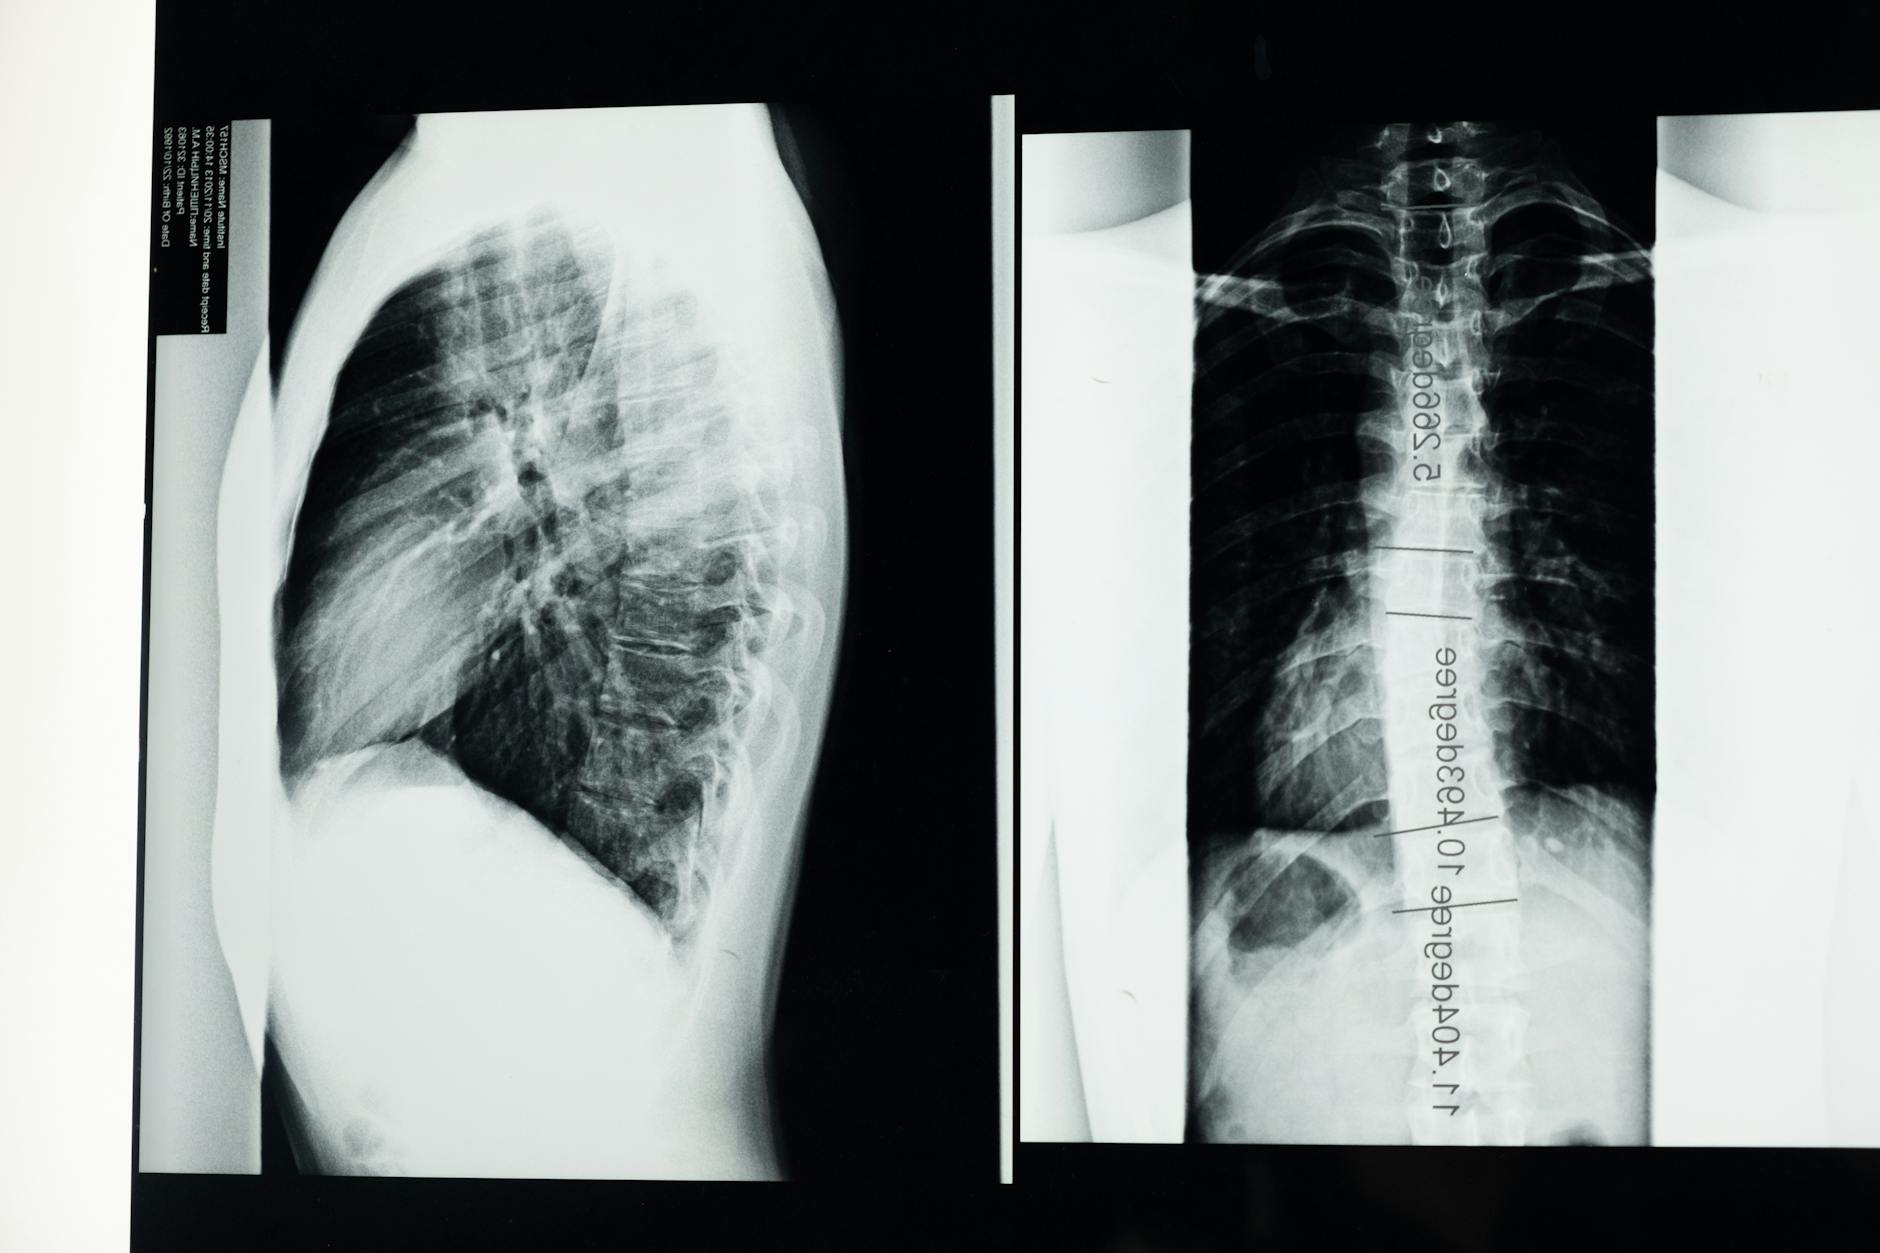

COPD is an umbrella term for an assortment of moderate respiratory conditions, all of which cause breathing troubles.

Two of the most well-known types of COPD are constant bronchitis and emphysema.

COPD just influences the lungs

“Bogus,” said Dr. Schachter. “COPD coincides with numerous comorbidities, including coronary illness, cellular breakdown in the lungs, hypertension, osteoporosis, and diabetes. The affiliation might be because of normal causative elements, just as ‘fundamental aggravation.'”